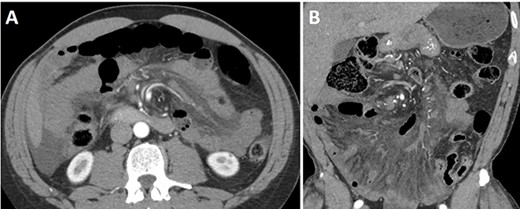

A 44-year-old Caucasian male presented with acute epigastric abdominal pain after strenuous exercise involving hyperextension and flexion (sit-ups) over an exercise ball. He reported two previous similar episodes after exercise that resolved spontaneously, and he had attributed to his new workout routine. His past surgical history was significant only for an umbilical hernia repair 18 months prior to presentation. A contrast-enhanced CT scan of the abdomen and pelvis was performed that demonstrated a significantly dilated stomach as well as a proximal loop of small bowel with edema of the mesentery and a whirl sign about the superior mesenteric artery (SMA) axis (Fig. 1). Diagnostic laparoscopy was performed for suspected midgut volvulus. Upon inspection, chylous fluid was found pooling in the mesentery adjacent to erythematous small bowel. The small bowel was carefully run from the ligament of Treitz to the ileocecal valve with no volvulus identified at the time of surgery. No evidence of ischemia or necrosis was identified. No adhesive disease or evidence of congenital malrotation was found. Peritoneal fluid sample was negative for malignancy though demonstrated a triglyceride level of 1451 mg/dl. The postoperative course was unremarkable, and the patient was discharged on postoperative Day 1. Six months later, the patient was admitted again with similar clinical presentation, preceded by abdominal exercises. Abdominal CT scan showed small bowel mesenteric edema and intra-abdominal fluid with a similar whirl sign about the SMA axis as seen in his prior CT scan 6 months earlier. The scan also demonstrated suspected partial superior mesenteric vein (SMV) thrombosis. We proceeded again with diagnostic laparoscopy and chylous ascites was found without obvious etiology. Conversion was then made to laparotomy which similarly failed to demonstrate any cause of the suspected transient intestinal volvulus or the chylous ascites. A confirmatory triple phase CT scan identified the presence of a non-occlusive thrombus of the SMV. He was started on anticoagulation for a 3-month course per hematology recommendations and discharged home uneventfully on postoperative Day 3 with recommendation to avoid any further strenuous exercise.

Abdominal and pelvis CT scan showed diffuse infiltration of the mesentery with twisting of the root of the mesentery, including the superior mesenteric artery and the other arterial branches. Additionally, there is moderate diffuse bowel wall thickening with several nonspecific distended small bowel loops. Diffuse inflammatory stranding throughout the mesentery. (A) Axial and (B) coronal views.